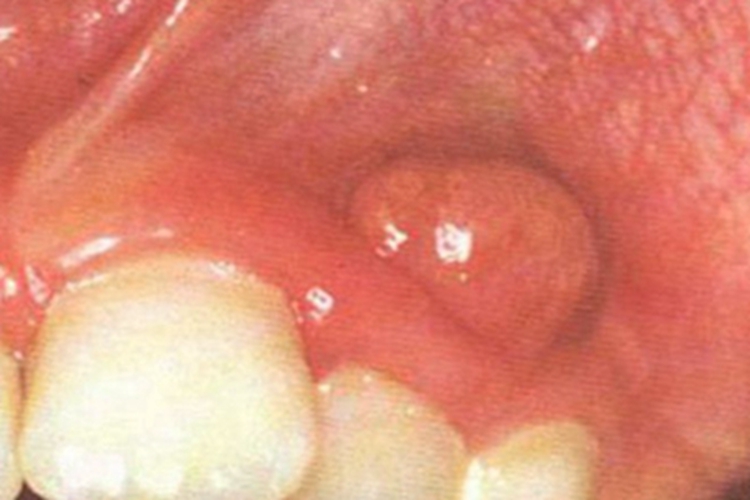

急性浆液性根尖周炎可表现为牙间隙处牙龈肿胀、充血,伴有牙根发痒、咬合时疼痛等症状,表面可出现浆液性渗出物,以血浆为主。